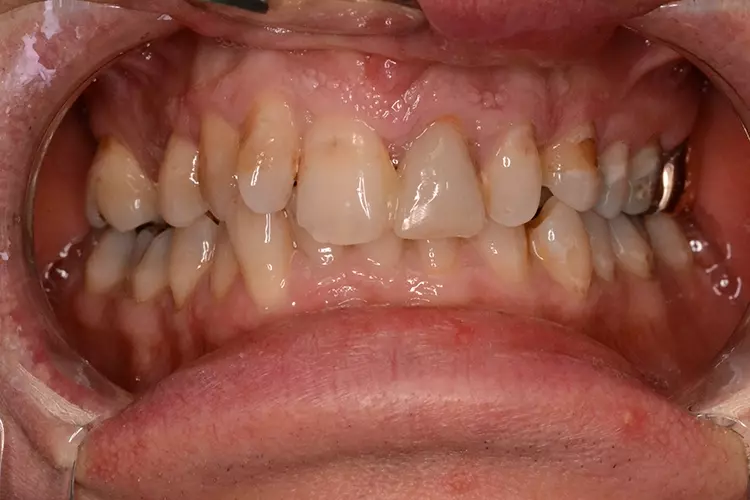

Neugestaltung der Front bei starken Zahnfehlstellungen

Bei dem heute 49-jährigen Patienten wurde seit Kindertagen versäumt, die Ober- und Unterkieferzahnbögen kieferorthopädisch auszurichten. Der Patient leidet seitdem stark unter seinen Zahnfehlstellungen.

Die Fraktur des stark elongierten Zahnes 21 war für den Patienten der Ausgangspunkt, sowohl die Front des Ober- als auch des Unterkiefers prothetisch überarbeiten zu lassen. Dabei wurde der frakturierte Zahn 21 durch ein navigiert eingesetztes Sofortimplantat ersetzt, während die verschachtelt stehenden Zähne 12 und 42 durch eine Brückenversorgung korrigiert wurden (Abb. 4a-j).